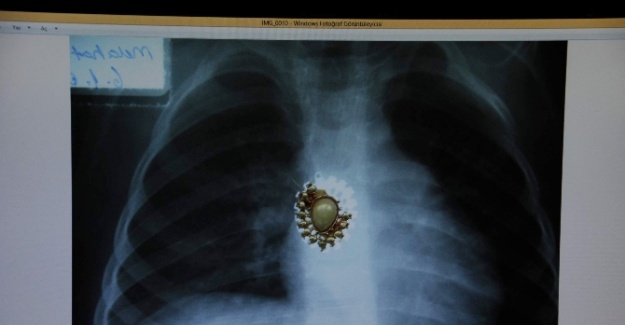

Koleksiyonda çıkan cisimlerden bilgiler veren Prof. Dr. Melikoğulları, “Yemek borusu içinde çocuklardan, iğne, kalemtıraş çıkarıyoruz. Sol akciğer bronşuna vida saplanan bir çocuk geç kalındığı için hayatını kaybetti. Soluk borusuna giden parça hastanın ileriki dönem için sakıncalıdır” ifadelerini kullandı.